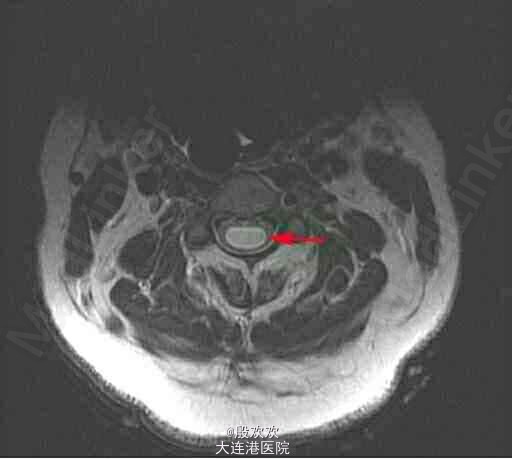

小脑扁桃体下疝并脊髓空洞症

链接【小脑扁桃体下疝畸形】 又名阿诺德-奇阿(Arnold–Chiari)畸形,为常见的先天性发育异常。是由于胚胎发育异常使小脑扁桃体下部下降至枕骨大孔以下、颈椎管内,严重者部分延髓下段、四脑室下部下蚓部也下疝入椎管内。常合并有脊髓空洞,也可引起脑脊液循环受阻引起脑积水。小脑扁桃体下疝畸形常伴其他颅颈区畸形如脊髓脊膜膨出颈椎裂和小脑发育不全等。可表现为头痛、头面部上肢力弱、肩臂部痛温觉减退、吞咽困 难、眩晕、恶心、共济失调、甚至瘫痪等症状。 【治疗方法】

符合手术适应征的患者应及早行手术治疗。症状出现2年内手术治疗效果最好,疼痛常可在术后缓解,肢体力弱不易改善,尤其已有肌肉萎缩者;脊髓空洞影像学改善率可高达90%...查看全部